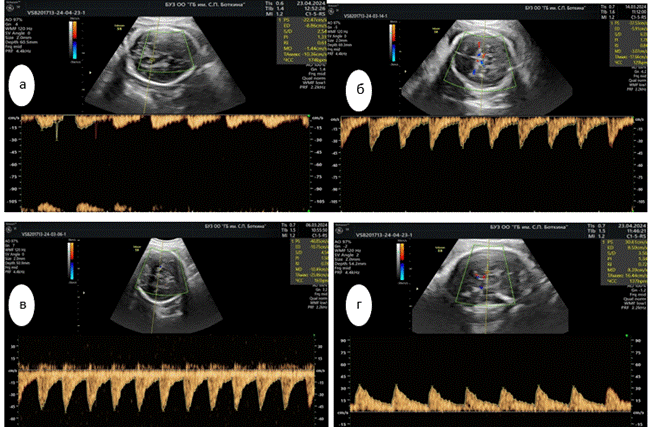

Обращало на себя внимание снижение периферического кровообращения в задней мозговой артерии (ЗМАPI) плода, о чем свидетельствовал показатель пульсационного индекса. Величина периферического кровотока мозгового кровообращения основной группы значительно отличались от уровня показателей контрольной группы и зависела от степени тяжести ПЭ. Уровень показателя ЗМА PI плода основной группы соответствовал 1,00, тогда как в группе сравнения был равен 0,79, а в контрольной группе достигал 0,66, что в 1.27 раза выше, чем в группе сравнения, и в 1.51 раза больше, чем в контрольной группе (рис. 2).

Рис. 2. Доплерометрические показатели церебрального кровотока в ЗМА: а) основная группа, тяжелая ПЭ; б) основная группа, умеренная ПЭ; в) группа сравнения; г) контрольная группа

Источник: составлено авторами на основе полученных данных в ходе исследования.